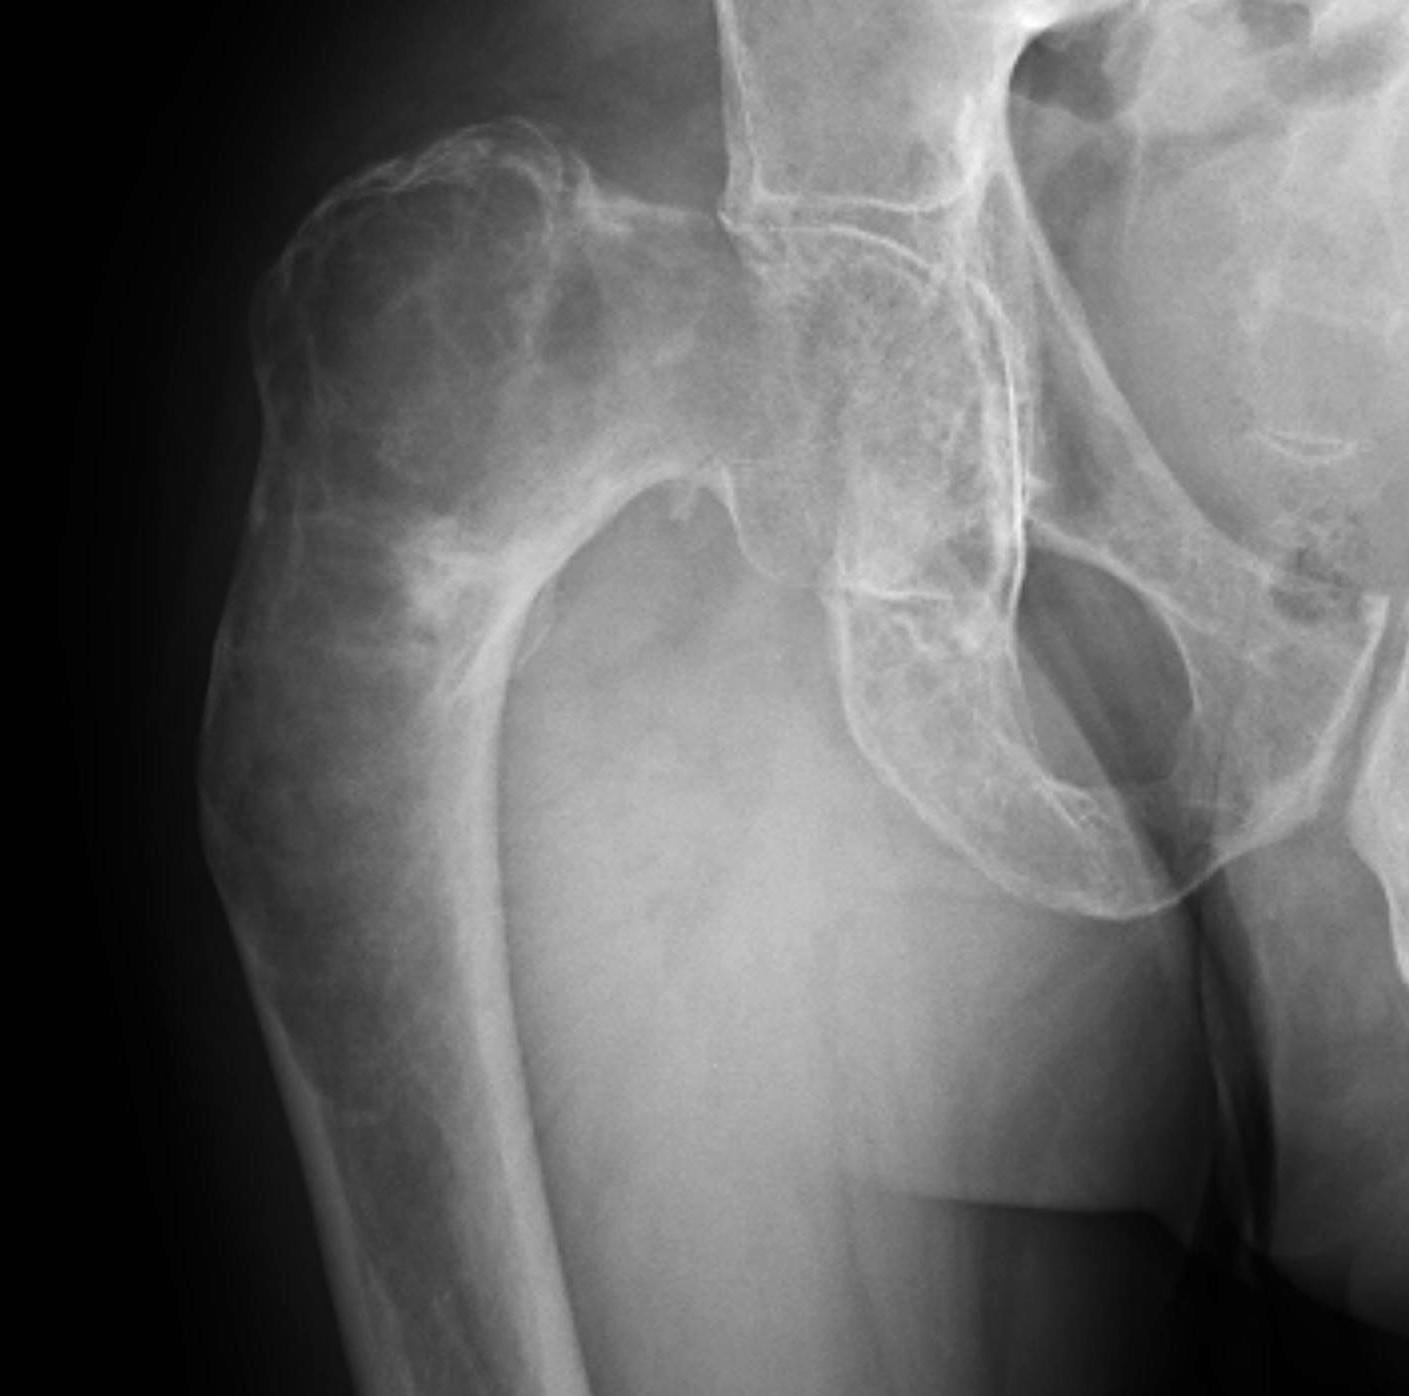

Intramedullary lucent diaphyseal lesion with 'ground glass appearance'

- thinned, slightly bulged cortex

- ± endosteal scalloping

- may have angular deformity / bowing

Coxa vara and Shepherd's Crook deformity of proximal femur

- Shepherd's Crook - anterior bowing of femur

- secondary leg length discrepancy

- pain, difficulty walking